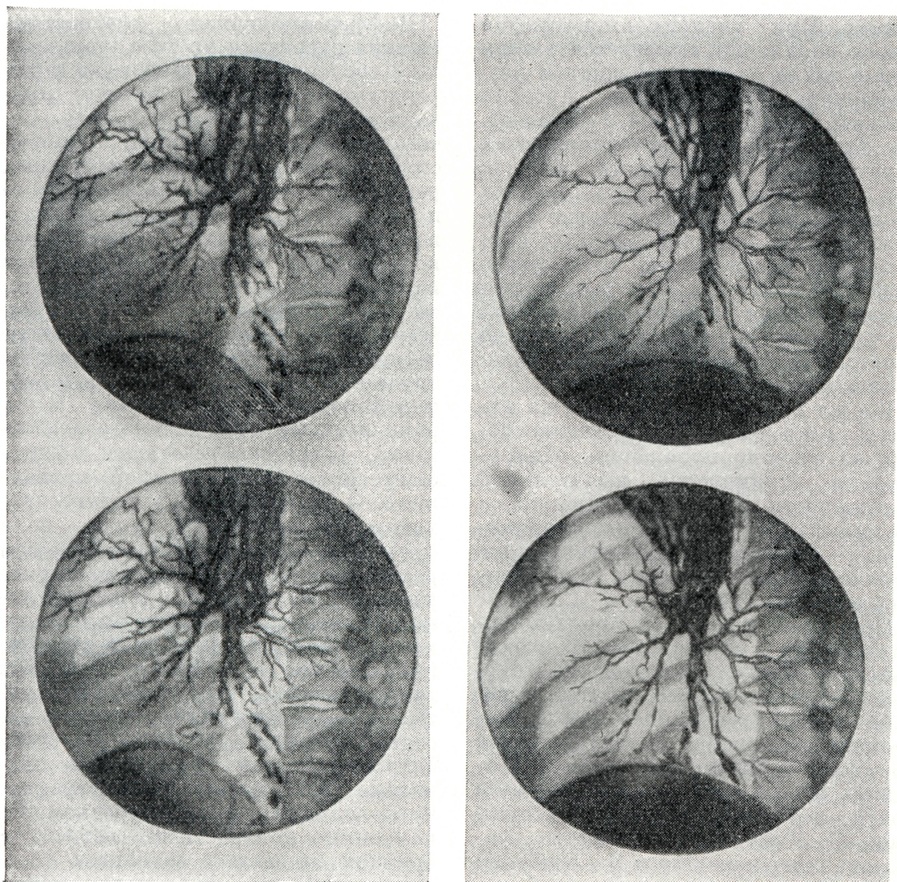

Б. вырисовываются на них как стойкие расширения бронхов, при которых диаметр поражённого ствола равен или превышает средний диаметр бронха предыдущего порядка. По форме различают цилиндрические, веретенообразные и мешотчатые Б. (рис. 2). Диаметр цилиндрического Б. больше диаметра дренирующего его бронха не более чем на 15%, диаметр веретенообразного Б.— на 15-30%, диаметр мешотчатого Б.— более чем на 30%. Почти у половины больных Б. одновременно наблюдаются разные формы расширений бронхов. При осложнении процесса абсцедированием на бронхограммах видны одна или несколько бронхоэктатических каверн, сообщающихся с поражёнными бронхами. Последние как бы впадают в полость абсцесса.

Остальные изменения в бронхиальной системе зависят от формы и происхождения Б. Для приобретённых Б. характерно неравномерное сближение бронхов в зоне поражения, значительная их деформация, угловые искривления и перегибы.

Наряду с расширенными бронхами обычно имеются бронхи с нормальным или даже суженным просветом. В значительной степени такая картина свойственна и так называемых ателектатическим Б., возникающим на почве предшествовавшего полного ателектаза. Поражение в этих случаях имеет строго выраженный долевой сегментарный характер.

При дизонтогенетических врождённых Б. бронхи в уплотнённой доле также сближены, но отличаются однотипностью изменений; все они равномерно расширены и заканчиваются булавовидными вздутиями, дальше которых контрастное вещество не проникает. Сегментарные бронхи могут быть недоразвиты, и тогда долевой бронх кажется удлинённым. При кистозных Б. сближенные бронхи заканчиваются множественными тонкостенными полостями. К периферии от кист контрастное вещество не поступает; там определяется недоразвитая лёгочная ткань с обеднённым лёгочным рисунком.